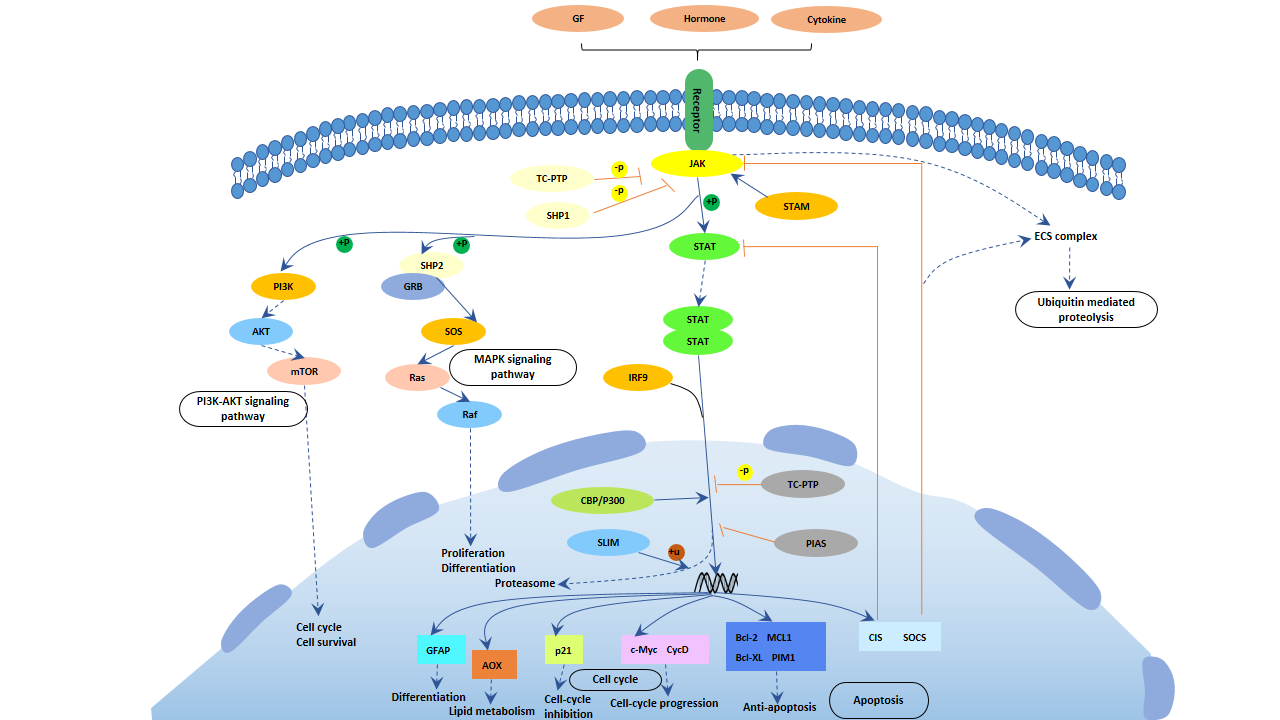

膠質纖維酸性蛋白-星形膠質細胞特異性標志物

膠質纖維狀酸性蛋白(glial fibrillary acidic protein, GFAP)屬于 III類中間絲狀體(IFs),特異地表達于中樞神經系統星形膠質細胞(AS)胞質內,可以作 為星形膠質細胞特異性標志物。GFAP與微管和微絲一起構成大多數真核細胞的細胞骨架,為 其他細胞或細胞外基質接觸的質膜提供機械支持,具有維護星形膠質細胞形態穩定、參與血 腦屏障形成、調節突觸功能等多種生物學功能,還參與細胞遷移、運動和有絲分裂。

圖1 星形膠質細胞

星形膠質細胞在大腦中含量豐富,是大腦 中最豐富的細胞類型,為神經元(包括神經遞質谷氨酸循環和營養因子釋放)提供結構和功能 支持,在神經生理活動、神經組織再生及免疫、多種神經疾病的發病中發揮重要作用。

作為星形膠質細胞內的主要骨架蛋白, GFAP在細胞核和細胞膜之間形成連接,參與細胞內細胞骨架重組、細胞黏附、維持腦內髓鞘 形成和神經元的結構以及作為細胞信號參與轉導通路等[8] [9],還參與細胞遷 移、運動和有絲分裂。膠質纖維酸性蛋白具有維護星形膠質細胞形態穩定、參與血腦屏障形 成、調節突觸功能等多種生物學功能。